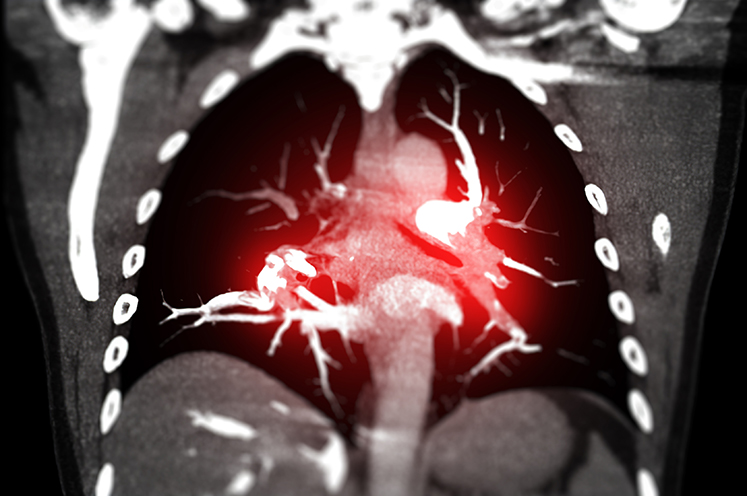

Lung and Pulmonary Care at Henry Ford

At the Henry Ford Health, we provide personalized care to help you manage symptoms of lung disease and breathe easier. As a leader in pulmonary (related to lungs and breathing) research, our lung program is well-known across Michigan and the U.S. We use the most advanced therapies to give you the care you need.

Our pulmonary and critical care medicine team treats conditions ranging in severity and symptoms. We have special expertise in COPD (chronic obstructive pulmonary disease), pulmonary fibrosis and pulmonary hypertension. Learn more about conditions we treat.

We offer a wide array of treatment options to help you get back to living your life, including a distinguished interventional pulmonology program that has helped develop new minimally invasive procedures. Everything from pulmonary rehabilitation to lung transplant is among our lung treatments.